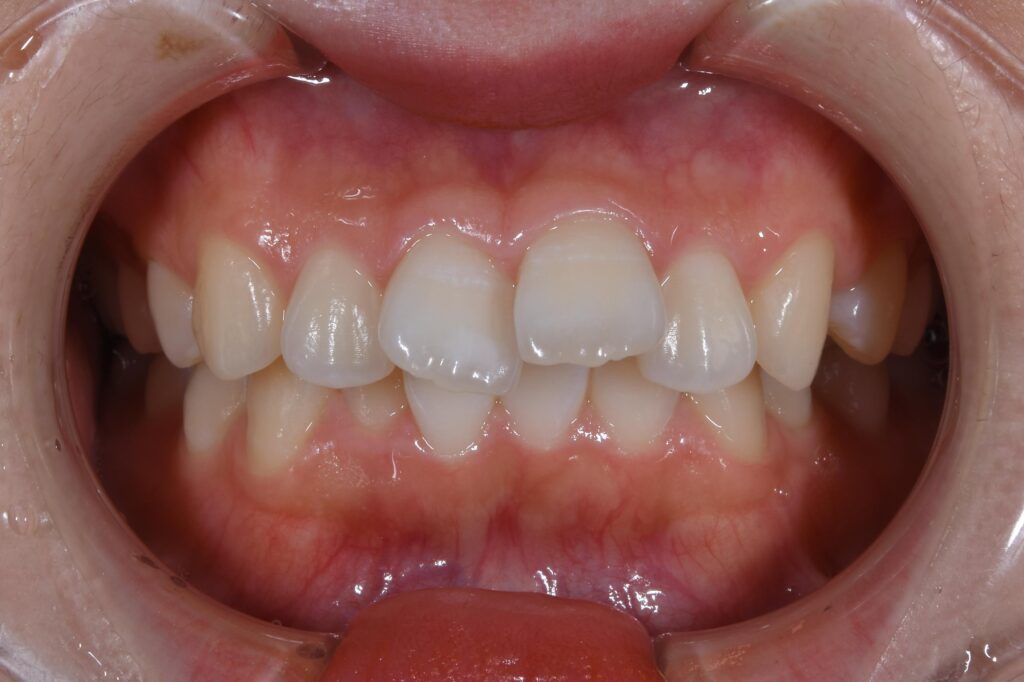

まずは術前の状態をお見せ致します。

【矯正治療前】

いかがでしょうか。

この患者様のお悩みは出っ歯。横からの写真で、出具合が顕著に確認できます。

治療計画として小臼歯を抜歯して歯を並べることにしました。